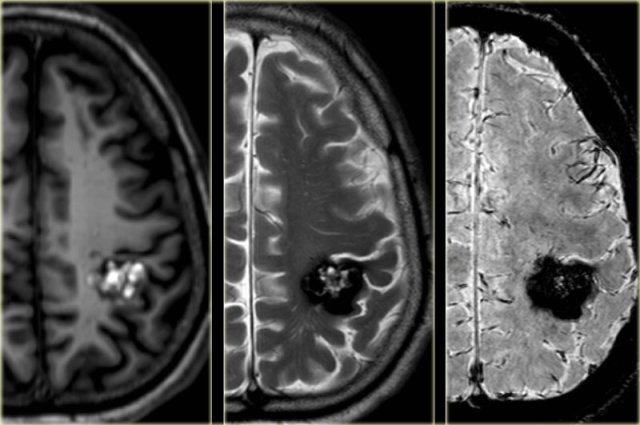

T2WI and T2* gradient echo show multiple cavernomas.

Notice the popcorn appearance with peripheral rim of hemosiderin on the T2WI.

The lesions are almost completely black on the gradient echo due to blooming artefacts.

T2* and susceptibility weighted imaging (SWI) markedly increase the sensitivity of MRI to detect small cavernomas.

The five black dots in the left cerebral hemisphere on the T2* are also cavernomas and are not visible on the T2WI.

Cavernoma in the postcentral gyrus on T1WI, T2WI and SWI.

Notice popcorn appeance and blooming artefact.

Same patient.

Notice the hemosiderin coating of the precentral gyrus consistent with superficial siderosis due to prior hemorrhage of the cavernoma (red arrowheads).